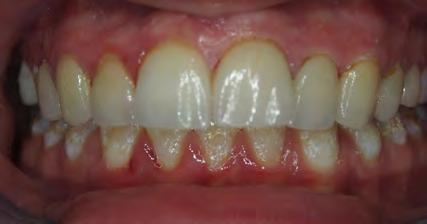

Two authors had access to the data and all information was de-identified. Study personnel made no contact with patients at any time throughout the study, and no PHI was recorded. Re corded data included diagnosis (clinical and/or pathologic), basic demographics (age, gender), and current prescription medica tions. For cases that were not biopsy-proven, the standard clinic protocol is that the clinical presentation must exhibit the charac teristic white Wickham striae for a patient to be given the clinical diagnosis of OLL or OLP (Figure 1). Any clinical diagnosis of OLL or OLP was rendered by one of four oral medicine experts in the Oral Medicine Clinic, and biopsy was performed in cases with any doubt.

Figure 1. Example of characteristic Wickham striae and reticular pattern on buccal mucosa used to clinically diagnose OLL and OLP cases. Erythematous areas also seen. Figure 2. Frequency and percent of study patients using specific medications with color-coded drug classes.